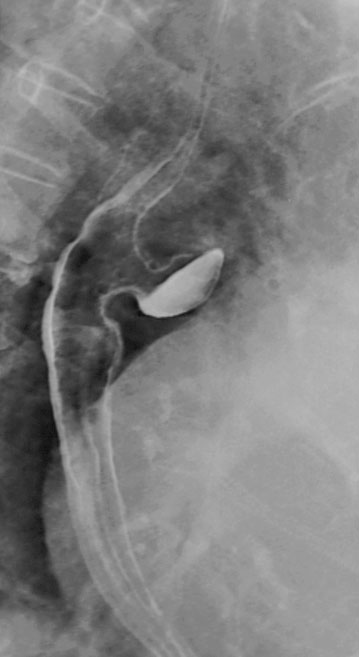

- Ösophagusbreischluck

- Mit Barium oder wasserlöslichem Kontrastmittel (Gastrografin)

- Das Divertikel stellt sich als abgerundete & kontrastmittelgefüllte Ausstülpung/ Ausbuchtung dar

Hellerhoff, CC BY-SA 3.0 , https://creativecommons.org/licenses/by-sa/3.0, via Wikimedia Commons